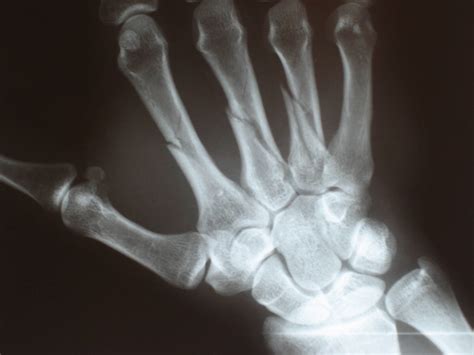

Fracture

Fracture